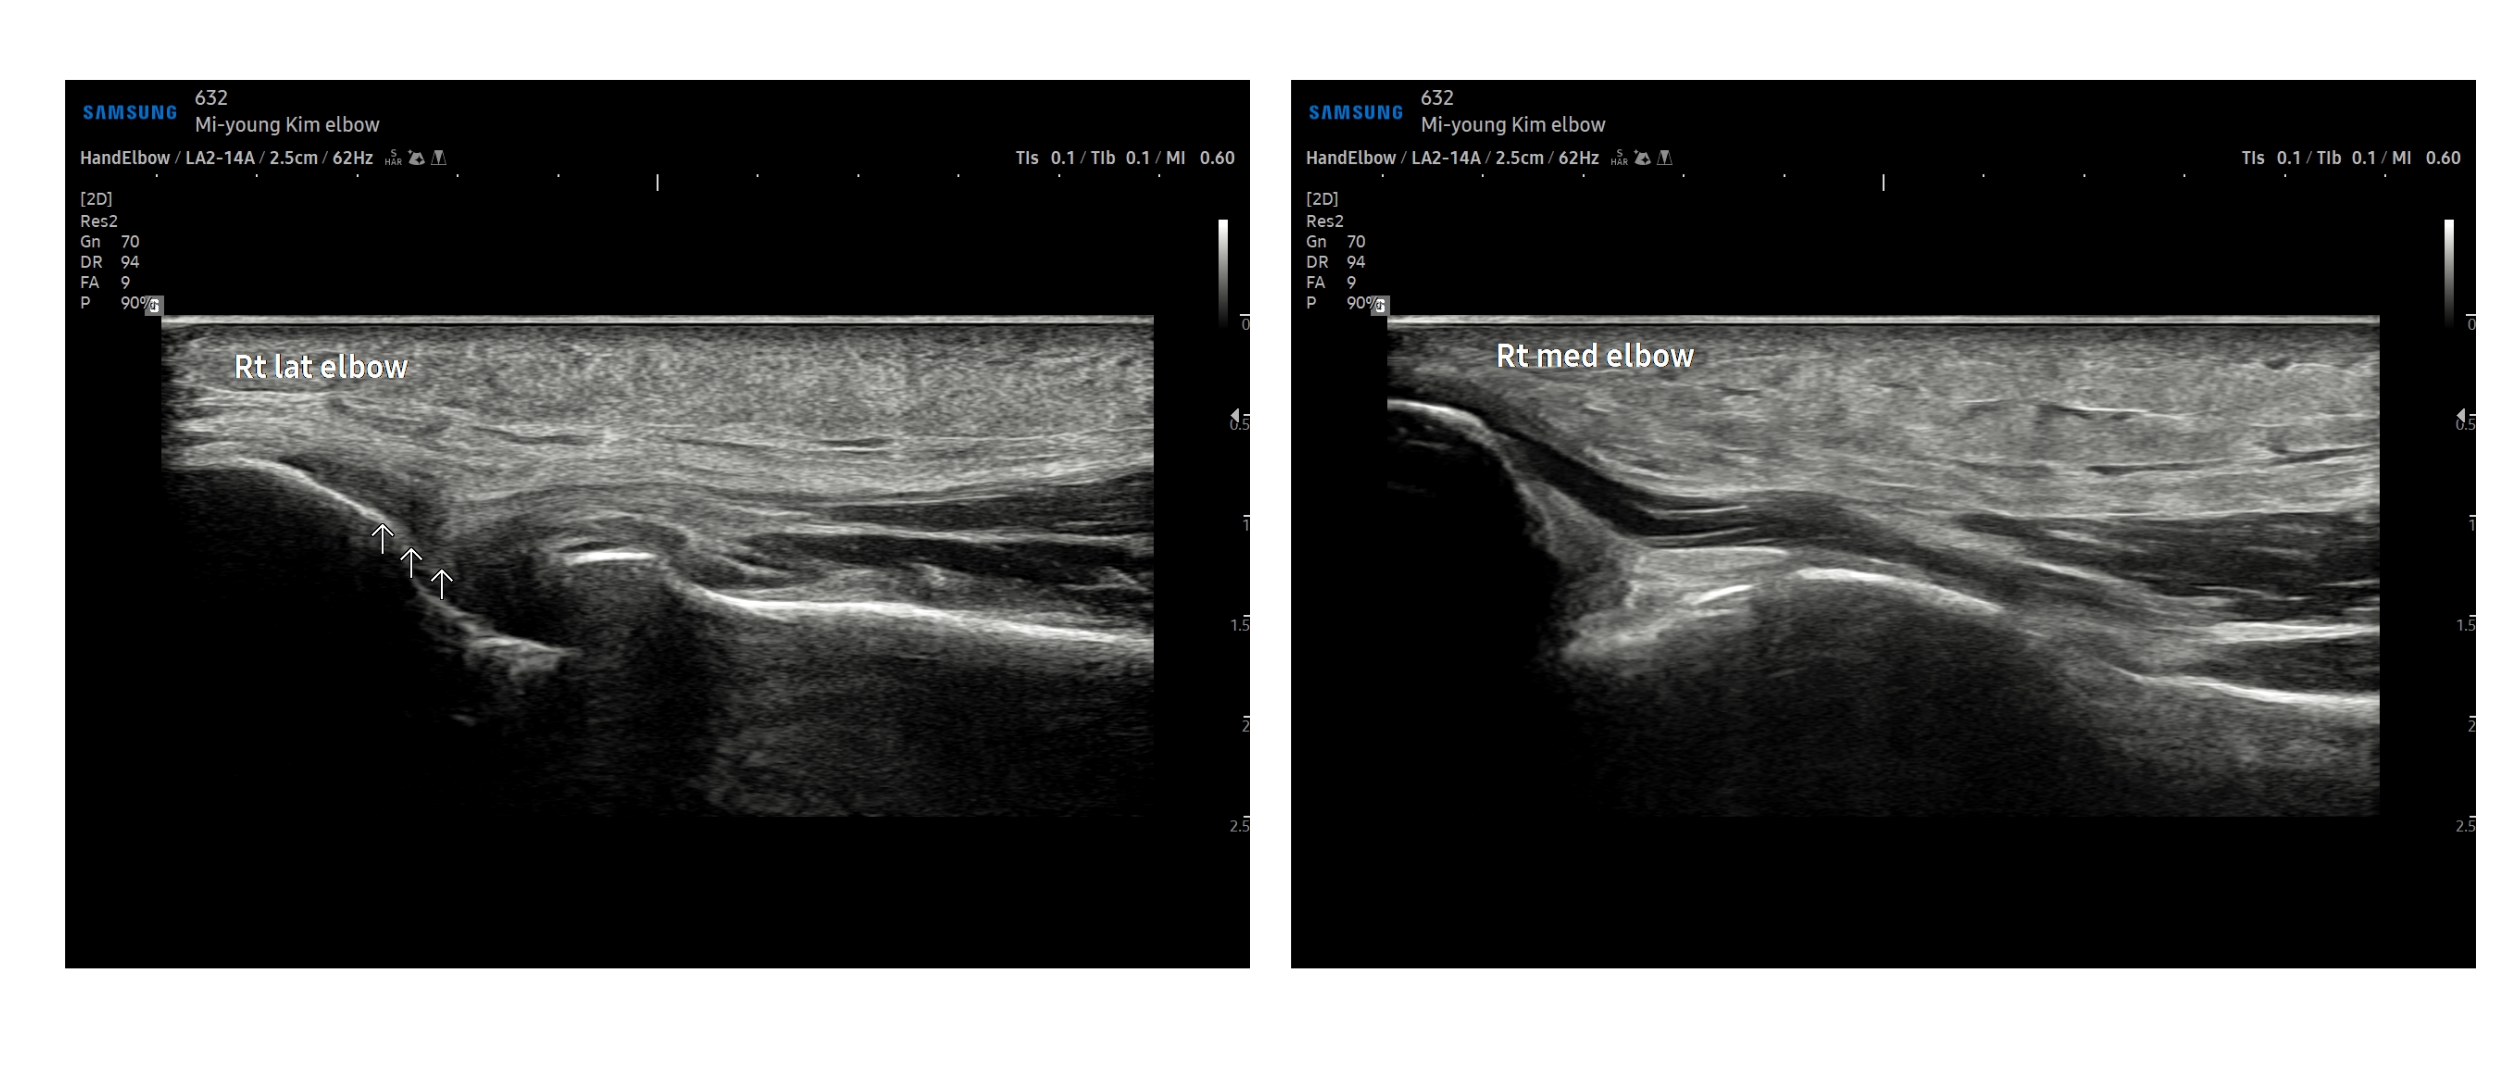

- 치료기간 : 25 . 6 . 30 ~ 25 . 11 . 7

- 치료횟수 : 20 회

[치료 전]

[치료 후]